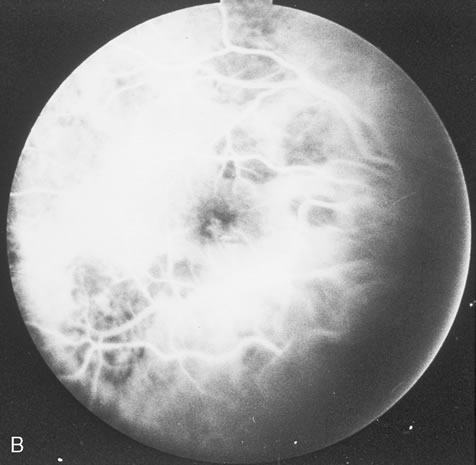

In primary ocular HSV infections, a severe follicular conjunctivitis with regional adenopathy is present. Vesicles may appear on the eyelid skin or lid margin, producing blepharitis (Fig. 3). Corneal involvement initially takes the form of a superficial punctate keratitis, which may progress to dendritic or geographic ulceration. Stromal infiltrates and uveitis are less common and relatively mild in primary disease. In uncomplicated cases, lesions usually heal completely in 2 to 3 weeks without scarring. Most cases of ocular HSV are recurrences. Recrudescent ocular herpes may take the form of dendritic or geographic ulcers, recurrent erosions, interstitial or disciform stromal keratitis, and anterior uveitis.3 HSV may also be an agent of retinitis and acute retinal necrosis (Fig. 4).

Corneal complications occur in the majority of patients with herpes zoster ophthalmicus. A punctate epithelial keratopathy with pseudodendrite formation is the earliest and most common lesion that occurs. Stromal infiltrates, disciform reactions, and rarely interstitial keratitis are also observed. Scarring and contracture of the lid margin often results in trichiasis, distichiasis, entropion, or ectropion. Corneal sensation is reduced, and neurotrophic ulceration, corneal melting, or perforation may ensue. Extraocular muscle involvement with facial paresis has been observed.11 The acute retinal necrosis (ARN) syndrome is most often caused by the herpes zoster virus, although occasionally it may be a result of herpes simplex infection.12 It is typically described in healthy patients although association with immunosuppressed patients has also been described. Granular, nonhemorrhagic areas of retinal necrosis may be observed in the fundus, often rapidly coalescing with resulting blindness often caused by retinal detachment. There is often an associated vasculitis and vitritis. In immunocompromised patients VZV or HSV retinitis may also take the pattern of progressive outer retinal necrosis (PORN) (Fig. 6). PORN differs from ARN in that the former is multifocal, localized to the outer retina, and is less often associated with vasculitis and vitritis.